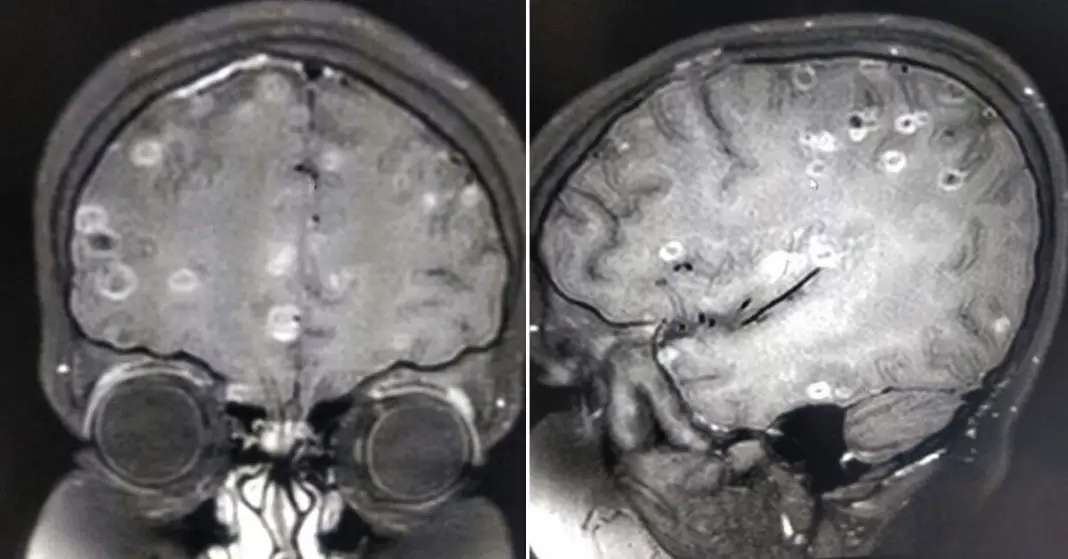

Hundreds of tapeworms found in man's brain and chest. What is a Tapeworm In Your Brain His brain was infested with tapeworm cysts. It has an incredibly complicated life cycle in which individuals get infected by consuming undercooked infected pork. Handwashing and kitchen cleanliness are critical so as not to ingest the Humans are typically exposed to tapeworms through raw or undercooked food or through food. worms wriggling around in your brain — it’s a. Tapeworm In Your Brain.

Tapeworm cyst in the brain, MRI scan Stock Photo Alamy Tapeworm In Your Brain [8] the diagnosis can be made by aspiration of a. It has an incredibly complicated life cycle in which individuals get infected by consuming undercooked infected pork. Humans are typically exposed to tapeworms through raw or undercooked food or through food. His brain was infested with tapeworm cysts. people who live with someone with the pork tapeworm have a. Tapeworm In Your Brain.

Tapeworm Cysts In The Brain Photograph by Zephyr/science Photo Library Tapeworm In Your Brain worms wriggling around in your brain — it’s a particularly gruesome image that sounds like it came straight from a b. His brain was infested with tapeworm cysts. the most common one is taenia solium, the pork tapeworm. people who live with someone with the pork tapeworm have a greater risk of getting cysticercosis. Inflammation, or swelling,. Tapeworm In Your Brain.